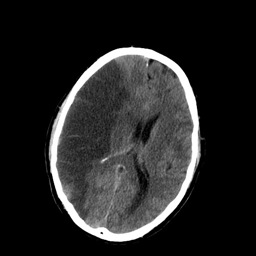

The image below shows typical changes in brain appearance following an ischemic stroke. Note the hypodense appearance of the right hemisphere and the obscuration in this area of gray and white matter. The left hemisphere provides a good comparison of normal appearing brain tissue.

Image courtesy of Lucien Monfils

As you can see, if either an ischemic or hemorrhagic stroke is seen on CT scan then a diagnosis can confidently be made and appropriate treatment can proceed. CT scan is fairly reliable for ruling out hemorrhagic stroke, but is an unreliable test for ruling out ischemic stroke (this likely has to do with the fact that changes in brain tissue resulting from ischemic stroke often do not appear for hours or days following the CVA).